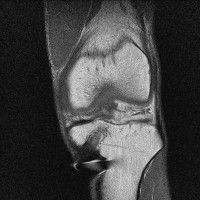

무릎 mri 간단히 봐주실 수 있으시나요 ㅠㅠ

안녕하세요 8년전 십자인대 수술하고 최근 무리한 운동에 무릎 불편감이 생겨서

mri 찍었습니다.

진단결과는 첫 찍은 병원에서 활액막염 이라는 진단을 받았습니다. 혹시 봐주실 수 있으실까요?

진단결과가 달라 혼란스럽습니다 ㅠㅠ

• 안녕하세요. 강성주 의사입니다.

올라온 MRI가 단편적이라서 정확한 진단에 어려움이 있지만 십자인대에는 큰 이상이 있지는 않은것 같으며, 무릎관절내 물이 있는 것으로 보아 활액막염의 진단이 맞을 것 같습니다.

하지만 단편적인 영상이기 때문에 촬영병원에서 정확한 판독지 등을 받으시는 것이 좋겠습니다.